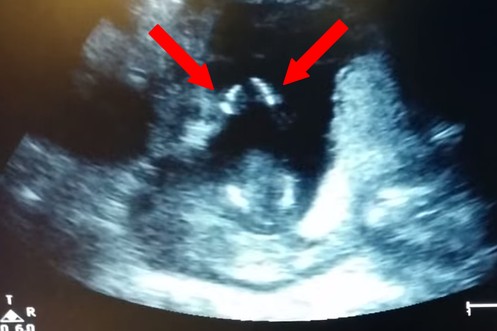

Ein klatschendes Baby ist nichts Besonderes, aber eins, das schon in Mamas Bauch applaudiert, ist uns noch nie untergekommen